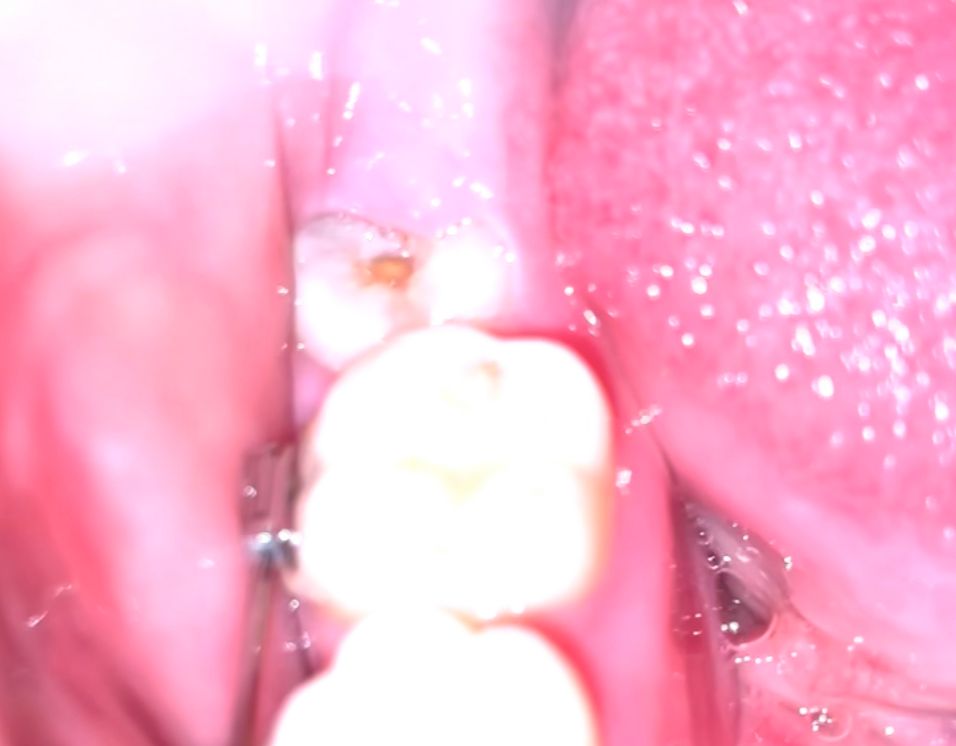

사랑니가 나고 있는데 사랑니 중앙에 움푹 파여 노랑-황토색 알맹이같은게 있습니다

충치인지.. 아니라면 뭔지 궁금합니다

사진상으로 보면 음식물이 껴 잇는것처럼 보입니다. 치과에 가셔서 확인을 해보시는게 좋을것같습니다. 만약 음식물이라면 제거를 하시면되지만 충치라면 사랑니라 발치를 하시는게 좋을수도 잇습니다.

사진 자료만으로는 정확한 판단이 어렵습니다만 충치일 가능성이 매우 높아 보입니다. 물론 음식물이 끼어 있어도 지금의 사진처럼 나올 수 있습니다. 정확한 평가를 위해서는 다음 교정 치과 방문시에 해당 부분에 대해서 한 번 평가를 해달라고 부탁해보시길 바랍니다.

임상 사진 만으로 봤을 때는 충치로 보입니다